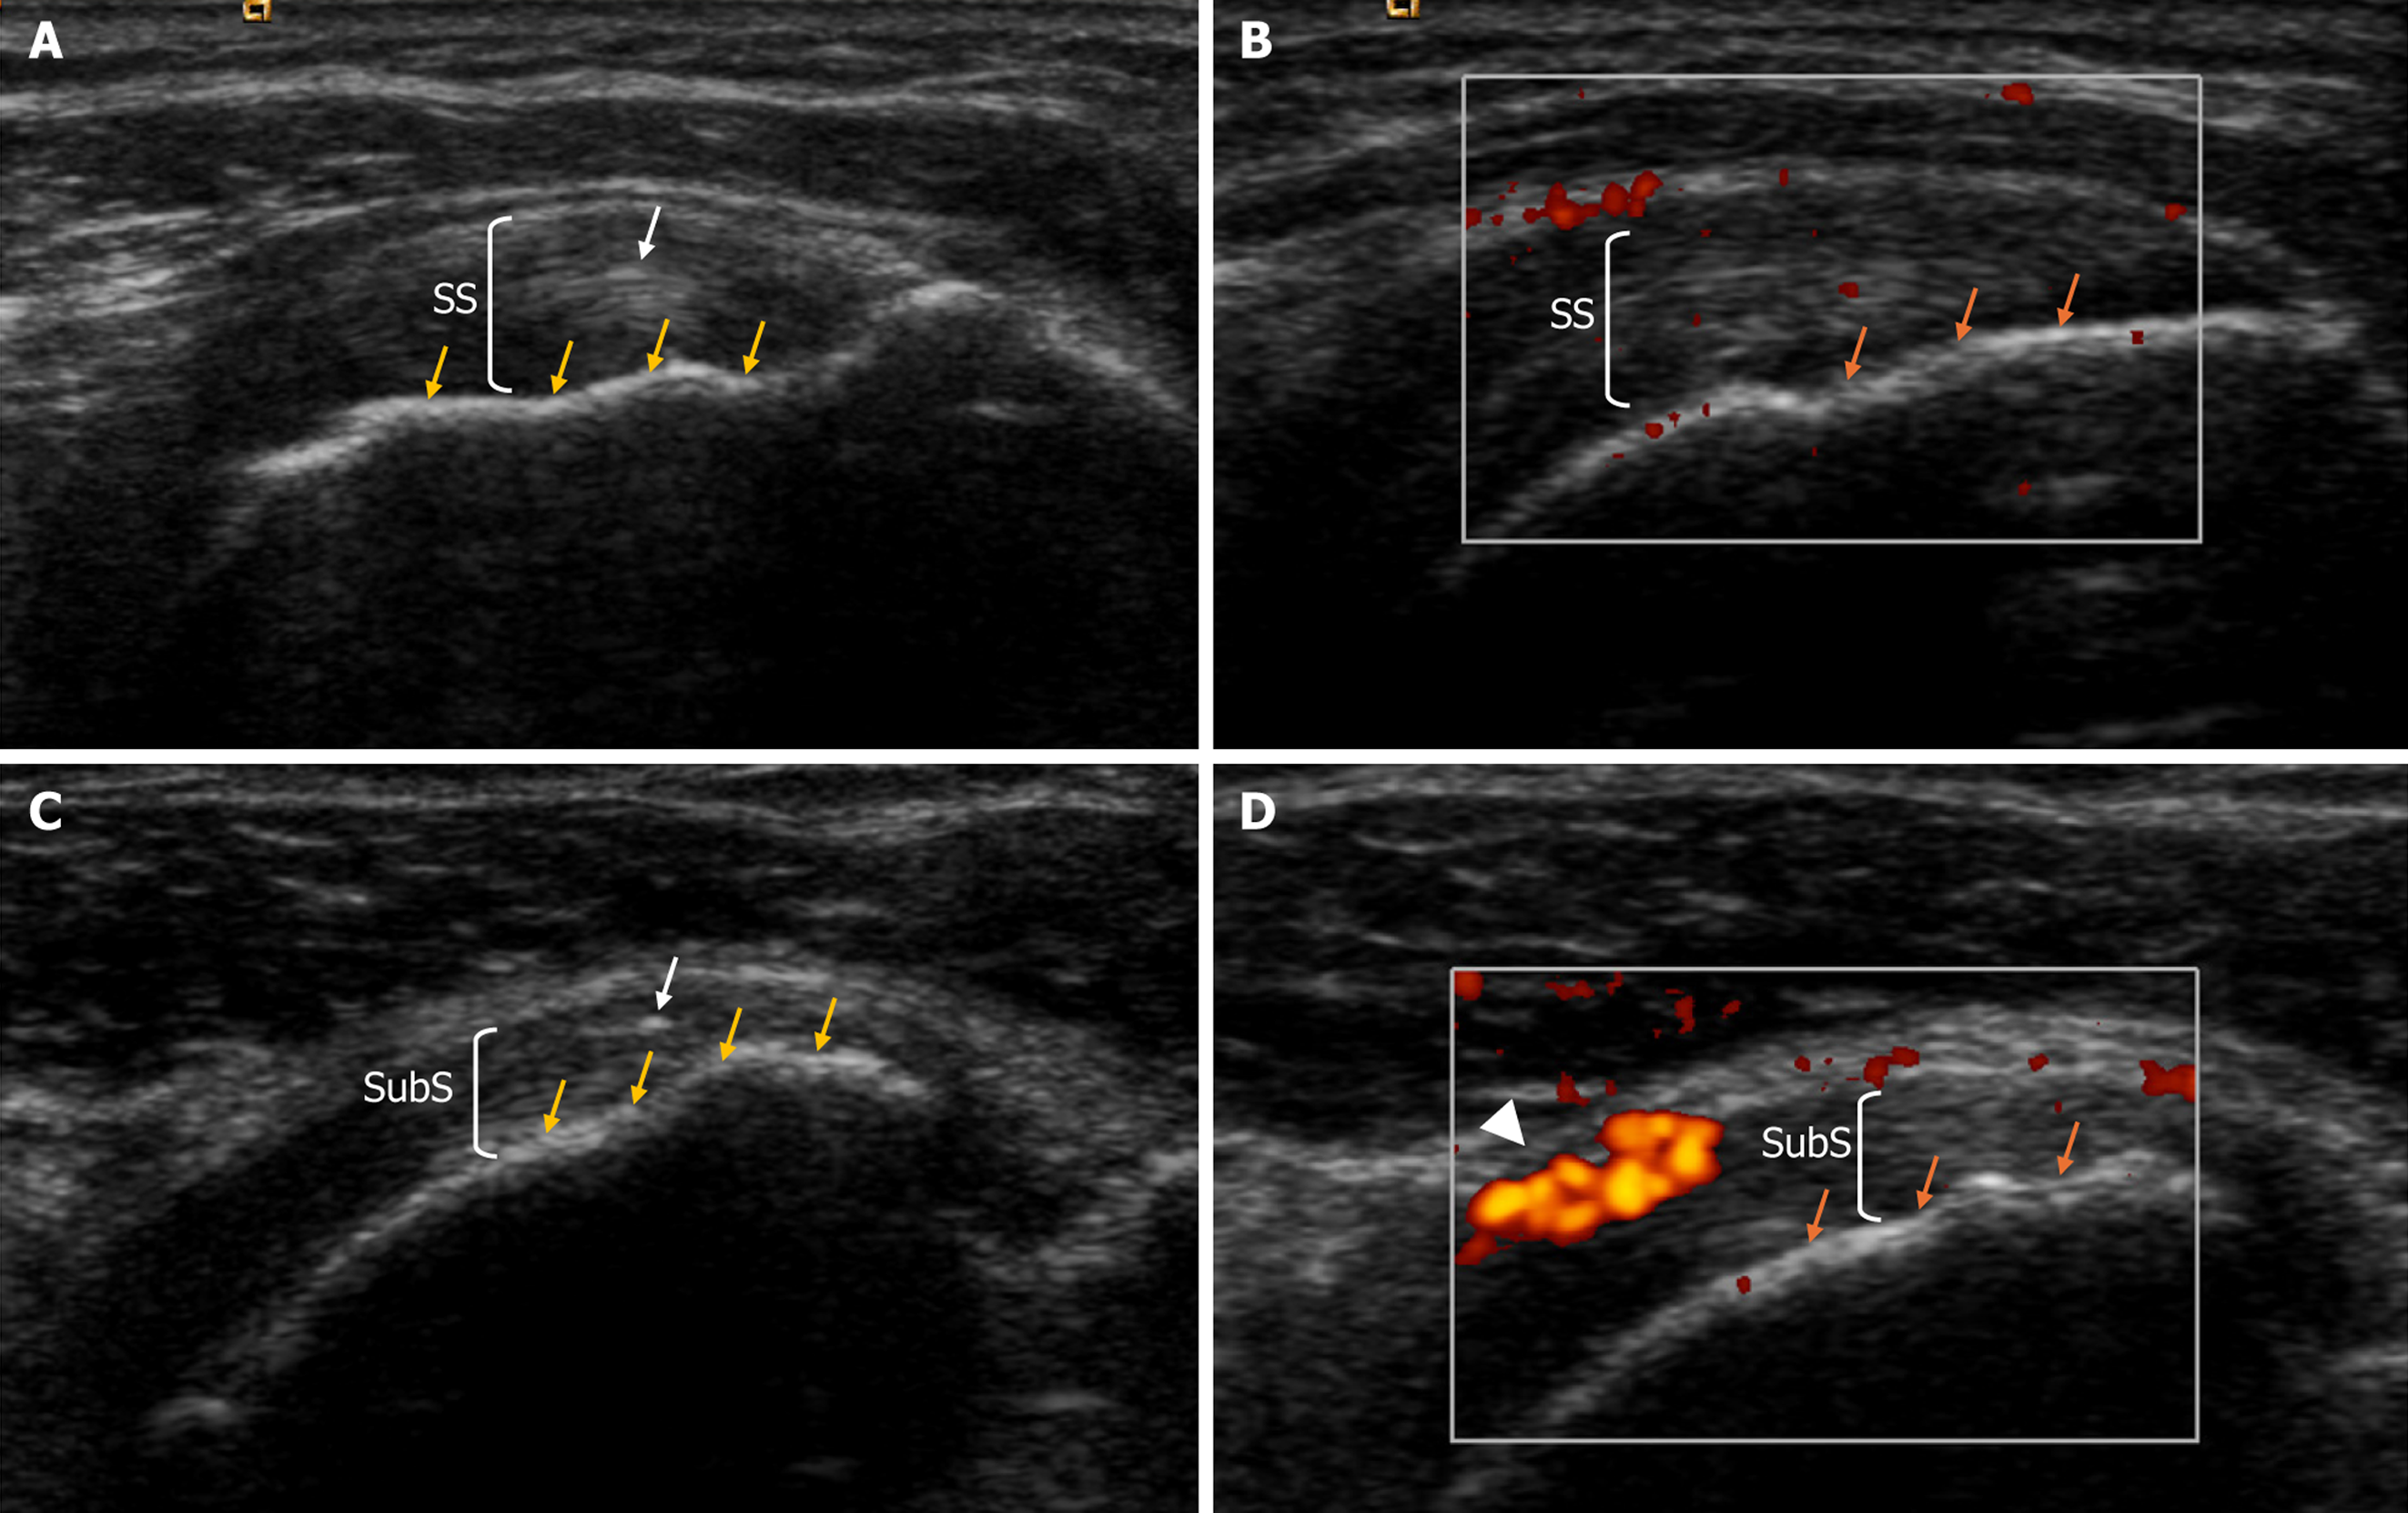

Figure 1 Left shoulder ultrasound evaluation of case 4.

A: Supraspinatus tendon of heterogeneous texture, calcium deposit (white arrow), but no bone cortical damage (yellow arrows); B: Doppler imaging showing isolated mild Doppler signal (red color); no significant signal is observed in the enthesis nor in the bone cortical (orange arrows), indicating the absence of inflammation; C: Subscapularis tendon, calcium deposit (white arrow), but no bone cortical damage (yellow arrows); D: Doppler imaging showing no signal in the enthesis nor in the bone cortical (orange arrows), indicating the absence of inflammation; intense Doppler signal in the subscapularis tendon’s superior fibers (red color, white arrowhead), indicating tendinopathy. SS: Supraspinatus tendon; SubS: Subscapularis tendon.